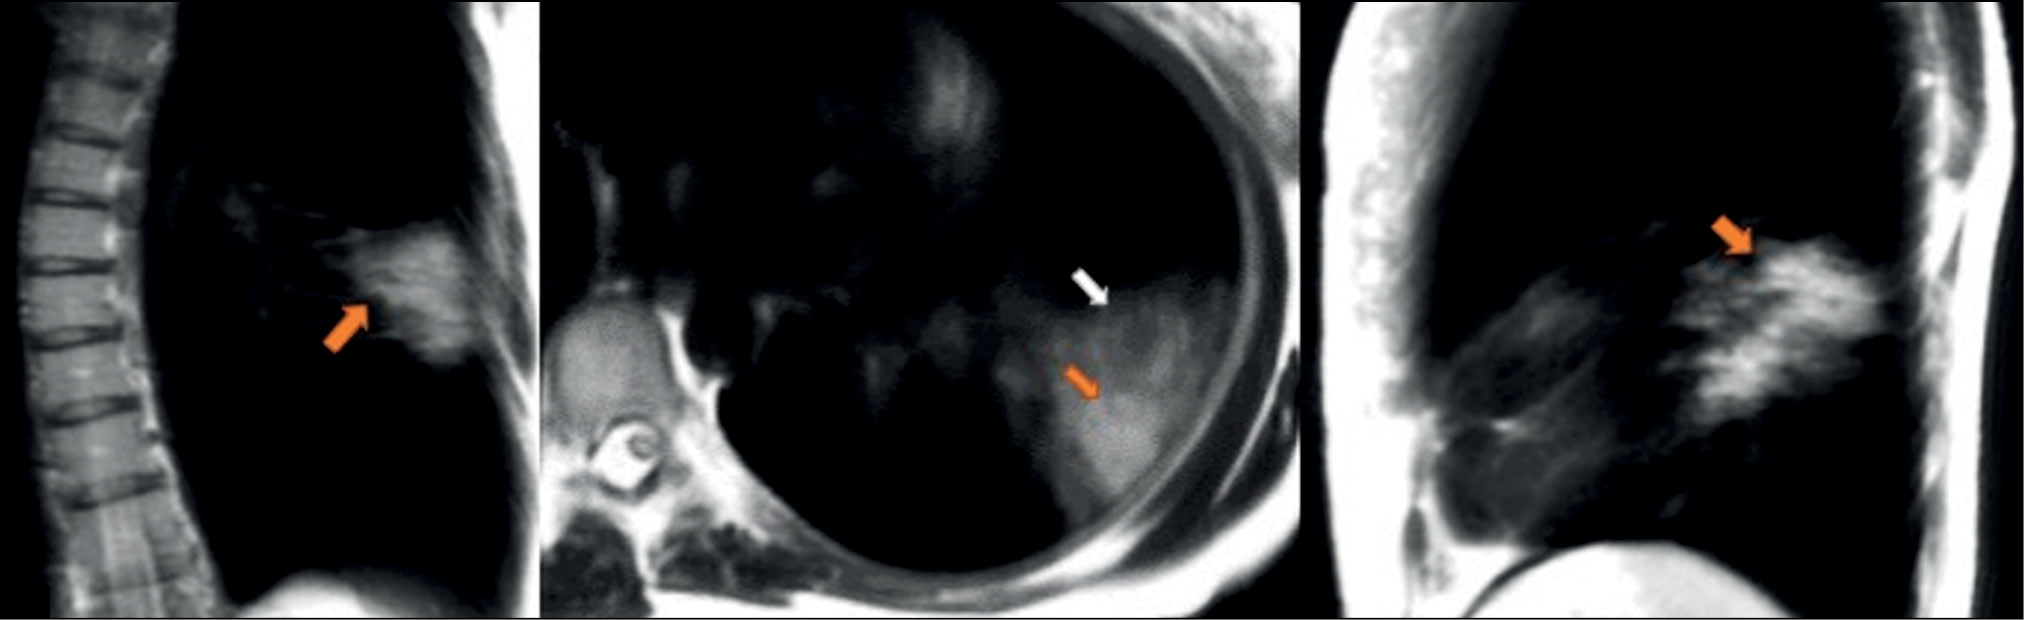

A patient (female, 25 years old) complained of a dry cough, high fever (up to 39°С), chills, and chest heaviness. She went to the hospital on the sixth day after the onset of the first symptoms, when they became extremely pronounced. Dynamic MRI showed a large area of increased signal in segments S6, S8, and S9 of the left lung’s lower lobe. An inhomogeneous increased signal was found during inhalation in the coronal, axial, and sagittal planes (Fig. 3). The signal intensity increased in the coronal and sagittal planes during exhalation (Fig. 4), with the increased visual size of the affected areas and the expanded “cloudy sky” area. These findings may be attributed to expiratory contraction of lung tissue during exhalation.

Figure 3. Dynamic magnetic resonance imaging of the lungs during inhalation in the coronal, axial, and sagittal planes. Orange arrows point to consolidation areas visible during inhalation (S6, S8, and S9). The white arrow points to the area with the “cloudy sky.”